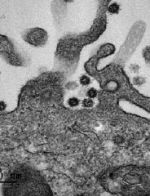

Vignette (© Philippe Roingeard et Sébastien Eymieux, Université de Tours).